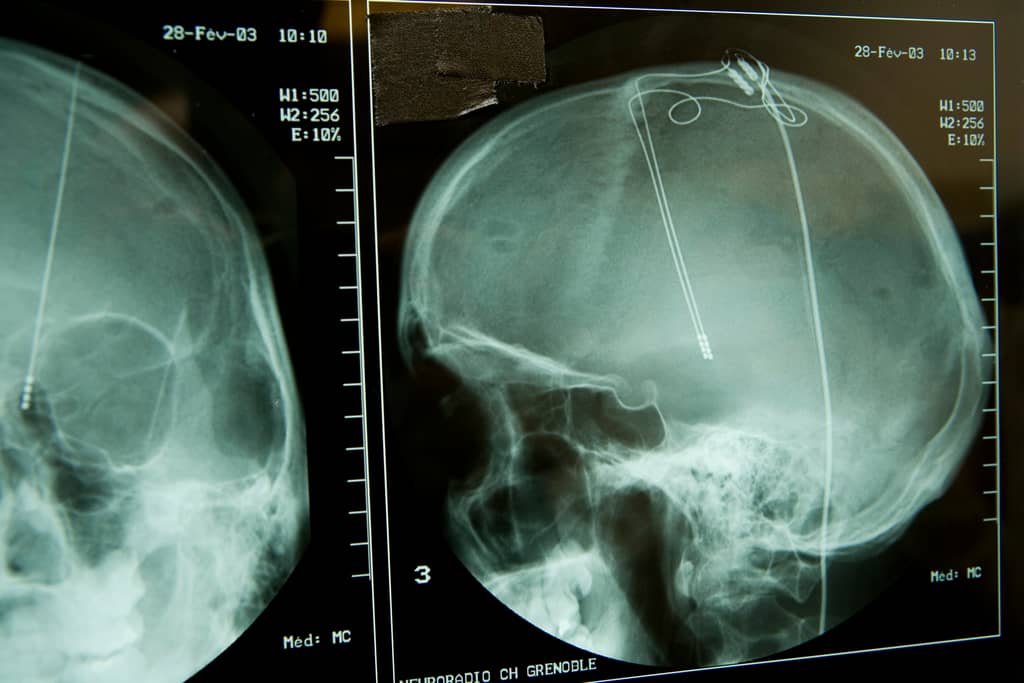

Inside your brain, there’s a very small section of tissue that some researchers believe is the very heart of the aging process.They also think this tiny but crucially important area holds clues that